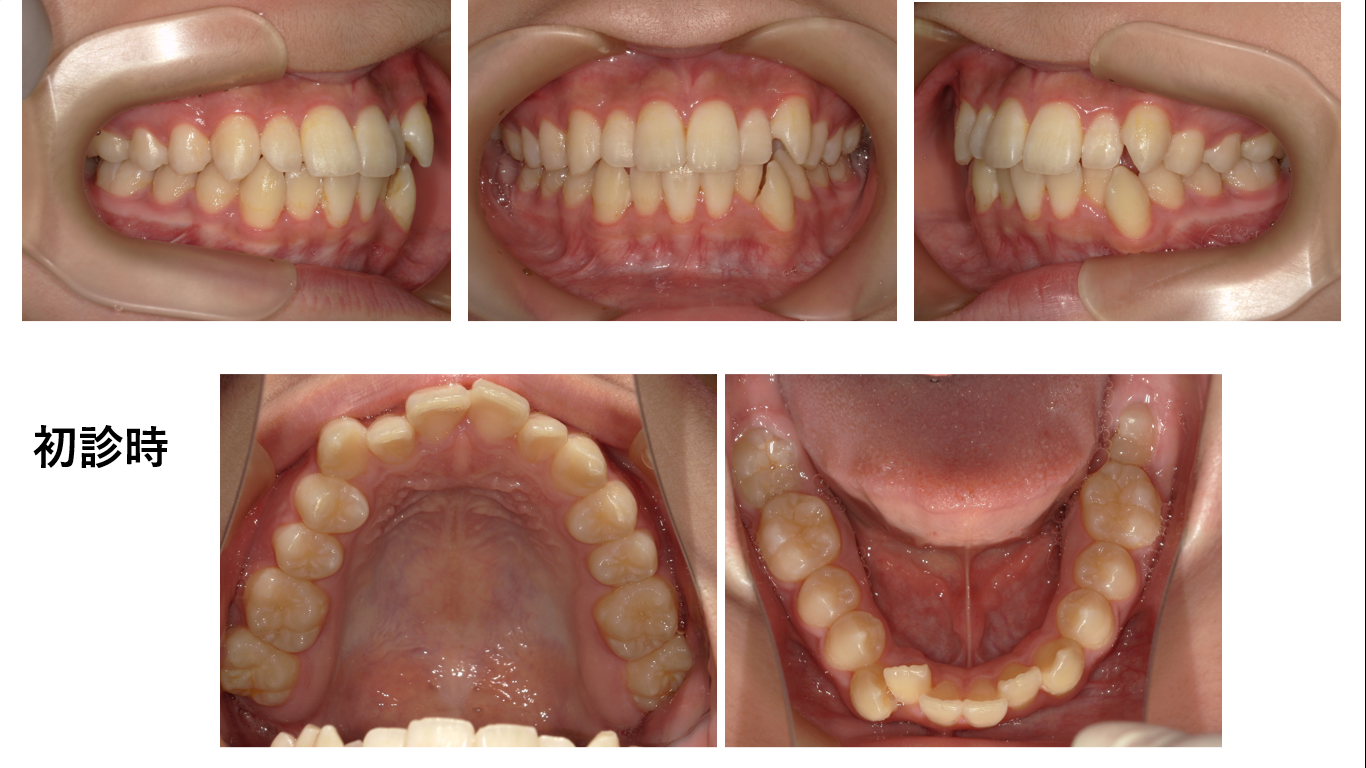

矯正症例141 AngleⅠ級 上下顎前突、ガミースマイル、口ごぼ

初診時15歳、治療期間3年、抜歯部位:上下顎4番、8番、治療費総額102万円(税込み)この症例も患者さんからHP掲載の許可を得ています。